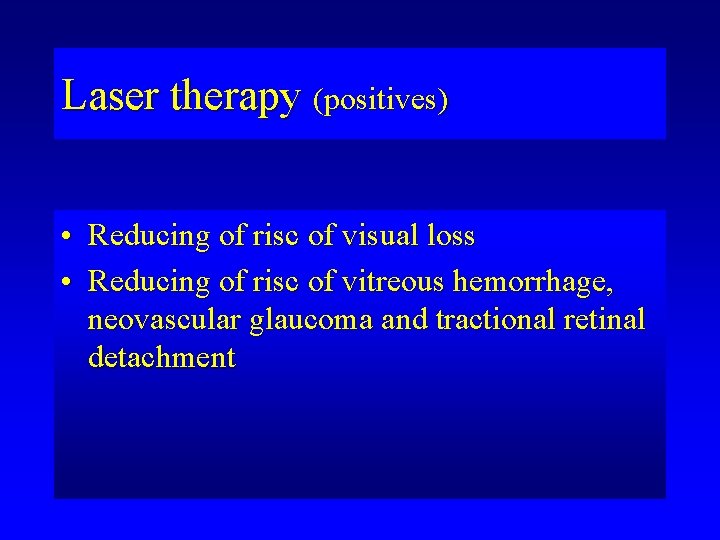

Laser therapy (positives) • Reducing of risc of visual loss • Reducing of risc of vitreous hemorrhage, neovascular glaucoma and tractional retinal detachment